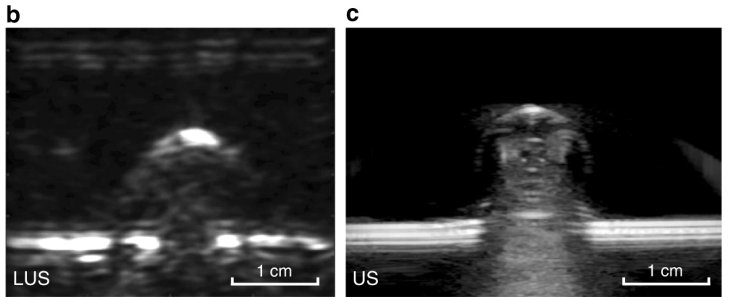

For now, this laser-based system can image a patient to six centimeters deep below the skin. It hasn’t matched the capabilities of traditional ultrasound techniques yet, but when testing on animal tissue and human subjects, the researchers found that the lasers could distinguish subtle features like the differences between muscle, fat deposits, and bone.